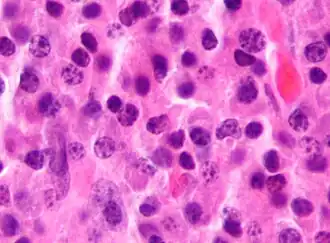

Micrograph of malignant plasma cells (plasmacytoma), many displaying characteristic "clockface nuclei", also seen in normal plasma cells. H&E stain. | |

Plasma cells are large lymphocytes with abundant cytoplasm and a characteristic appearance on light microscopy. They have basophilic cytoplasm and an eccentric nucleus with heterochromatin in a characteristic cartwheel or clock face arrangement. Their cytoplasm also contains a pale zone that on electron microscopy contains an extensive Golgi apparatus and centrioles. Abundant rough endoplasmic reticulum combined with a well-developed Golgi apparatus makes plasma cells well-suited for secreting immunoglobulins.[4] Other organelles in a plasma cell include ribosomes, lysosomes, mitochondria, and the plasma membrane.

Plasmacytoma, multiple myeloma, Waldenström macroglobulinemia, heavy chain disease, and plasma cell leukemia are cancers of the plasma cells.[33] Multiple myeloma is frequently identified because malignant plasma cells continue producing an antibody, which can be detected as a paraprotein. Monoclonal gammopathy of undetermined significance (MGUS) is a plasma cell dyscrasia characterized by the secretion of a myeloma protein into the blood and may lead to multiple myeloma.[34]